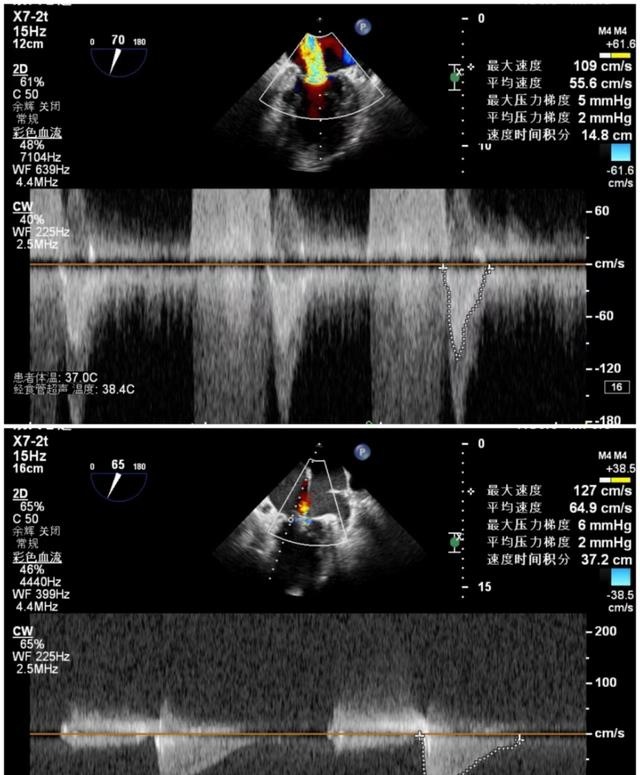

7月9日上午心内科联合麻醉科、胸外科等多学科,共同为陈奶奶开展手术,术前二尖瓣大量反流,反流程度5+,肺静脉反流明显,术后二尖瓣少量反流,反流程度1+,肺静脉反流消失,手术顺利结束。

手术前后二尖瓣压差